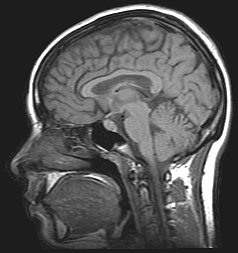

18 De scanner in, maar welke?

a Benoem de scanners. Je mag kiezen uit: CT, MRI en PET.

A

B

C

b Kies de juiste foto’s erbij.

1

2

3

c Wat betekent dit bord?

De oplossing is:

a.   A = MRI, B = PET, C = CT

b.   1 (PET), 2 (MRI), 3 (CT)

c.   Verboden voor pacemakers.